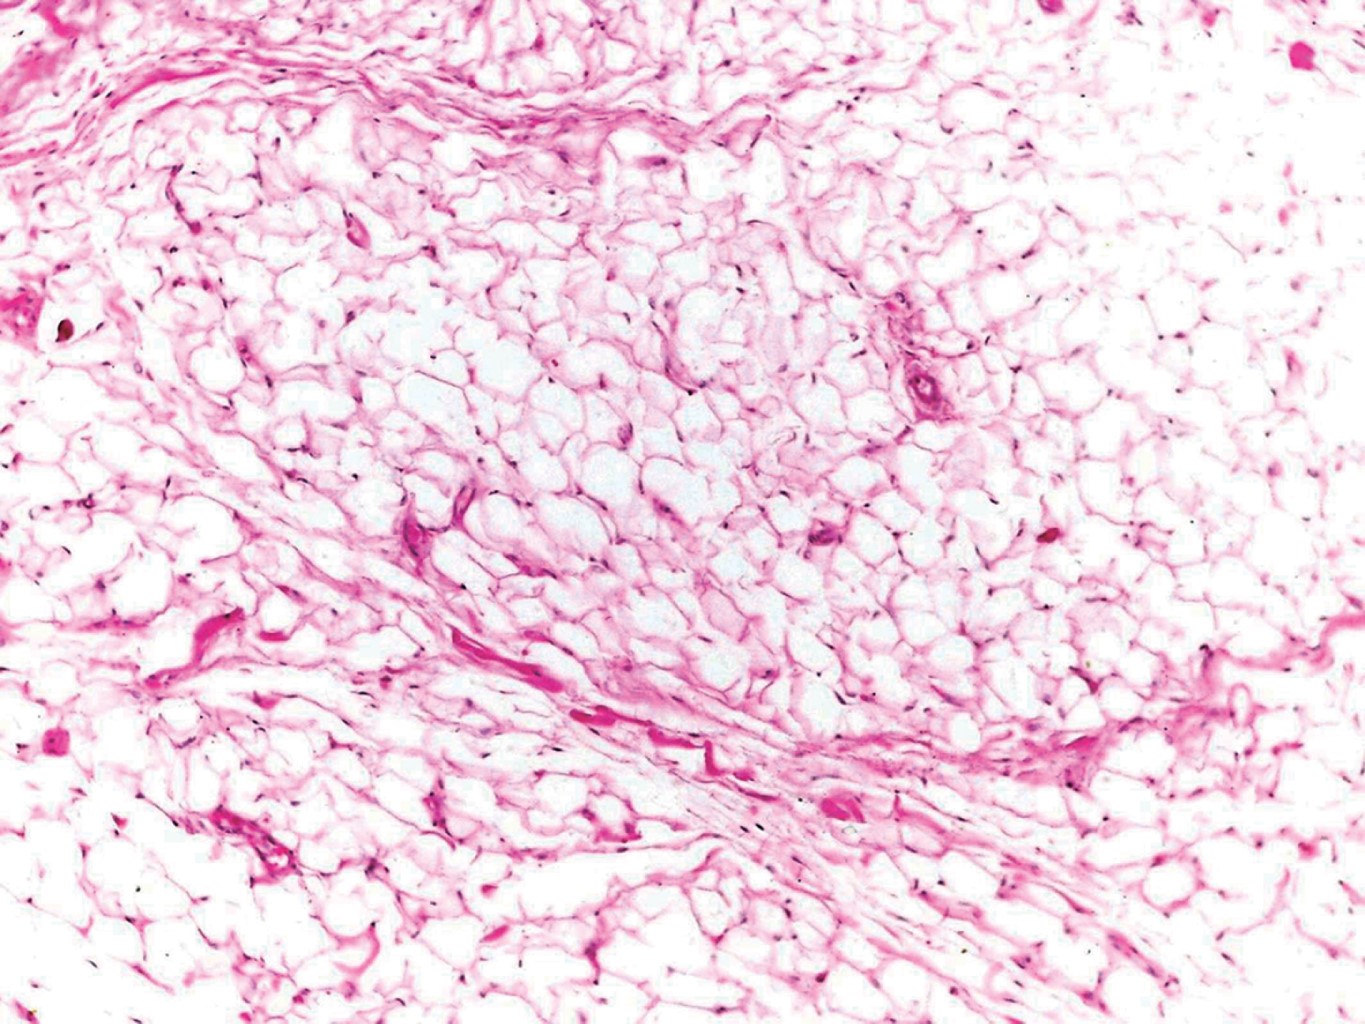

Con el diagnóstico presuntivo de lipoma en mucosa labial inferior, el paciente es referido al Servicio de Cirugía Dermatológica, en donde se realiza extirpación de la lesión con cierre directo (Figuras 2 y 3). El estudio histopatológico describe al corte la presencia de una neoformación bien circunscrita, constituida por numerosos adipocitos maduros de características normales, con algunos vasos dilatados y congestionados (Figuras 4, 5 y 6) confirmando con estos hallazgos el diagnóstico de lipoma. En el seguimiento postoperatorio del paciente únicamente se presenta cicatriz eutrófica; dos meses posteriores a la cirugía se da de alta.

Debido al lento crecimiento y evolución asintomática de estas neoformaciones, el diagnóstico suele retrasarse hasta que el tumor causa problemas funcionales o estéticos en los pacientes. Se calcula que el promedio de tiempo al momento de ser diagnosticado es de 2.6 años.5,7,8 El diagnóstico definitivo se establece mediante estudio histopatológico con tinción de rutina (hematoxilina y eosina), el cual muestra proliferación bien circunscrita de adipocitos maduros idénticos al tejido adiposo normal, aunque se ha reportado en algunos casos metaplasia cartilaginosa y ósea. En los lipomas intramusculares se pueden observar fibras de músculo estriado.9 Los lipomas, a diferencia del tejido adiposo normal, suelen estar bien circunscritos, en ocasiones encapsulados, pero sin vascularidad. Por otra parte, el tamaño de los adipocitos suele ser mayor en los lipomas, no obstante, la mayoría de las veces no es posible distinguir entre ambas entidades.10 En algunos casos puede haber hallazgos asociados a traumatismo o sobreinfección, como la presencia de infiltrado inflamatorio, necrosis o licuefacción grasa.4

Figura 6